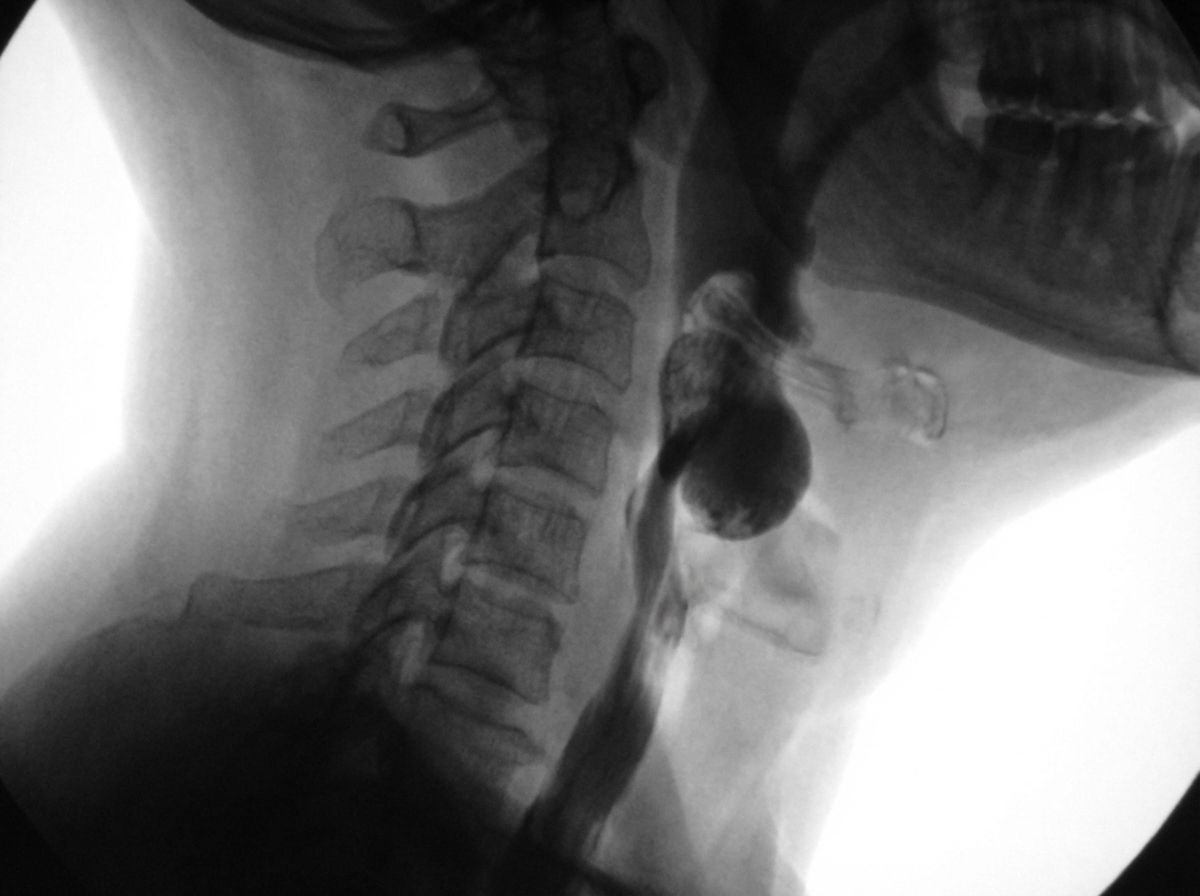

A 74-year-old male complains of bad breath, regurgitation of food during his sleep, and weight loss. For several months he has also had trouble swallowing solids. He denies fever, chills, and nausea. The patient does not smoke cigarettes and does not drink alcohol. Barium swallow study with fluoroscopy is obtained. Which of the following is the most likely underlying cause of the patient's condition?

Explanation: ***Defect in the muscular wall of laryngopharynx*** - This describes **Zenker's diverticulum**, which occurs due to weakness in **Killian's triangle** (between cricopharyngeus and thyropharyngeus muscles), causing a posterior pharyngeal pouch. - Classic triad includes **halitosis** (bad breath), **nocturnal regurgitation** of undigested food, and **dysphagia** for solids, which matches this elderly male patient's presentation. *Achalasia* - Characterized by failure of the **lower esophageal sphincter** to relax, causing dysphagia for both liquids and solids. - Barium swallow would show a classic **"bird-beak" appearance** with smooth tapering at the gastroesophageal junction, not a pharyngeal pouch. *Gastro-esophageal reflux disease* - Typically presents with **heartburn**, **acid regurgitation**, and chest pain, especially when lying down. - Does not cause **nocturnal regurgitation** of undigested food or the specific constellation of symptoms described. *Diffuse esophageal spasm* - Causes **chest pain** and dysphagia due to uncoordinated esophageal contractions. - Barium swallow shows a **"corkscrew" or "rosary bead" appearance**, not regurgitation of undigested food or halitosis.